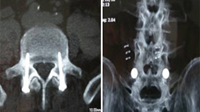

Izquierda: escáner de control post-operatorio de la caja intersomática PEEK

colocada por técnica percutánea. Derecha: doble fusión intervertebral con caja

de PEEK con incisiones de solo 12 mm y bajo anestesia local